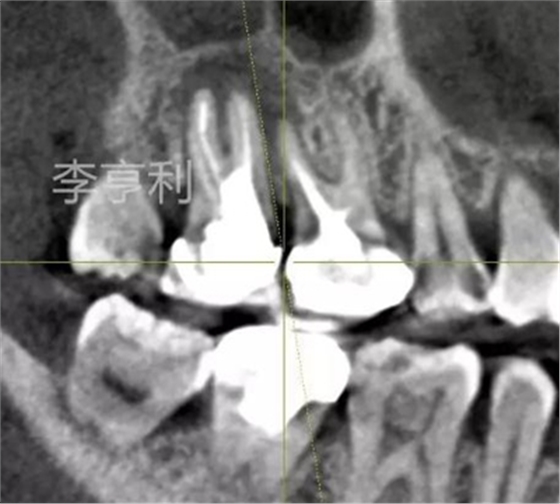

【輔助檢查】: CBCT見17冠部大面積充填物阻射影,接近髓室底,根管內(nèi)充填物錐度尚可,距根尖均為2mm以內(nèi),根尖周大范圍阻射影主要在頰根區(qū)域,波及16的DB根尖區(qū)域,頰腭側(cè)骨板完整